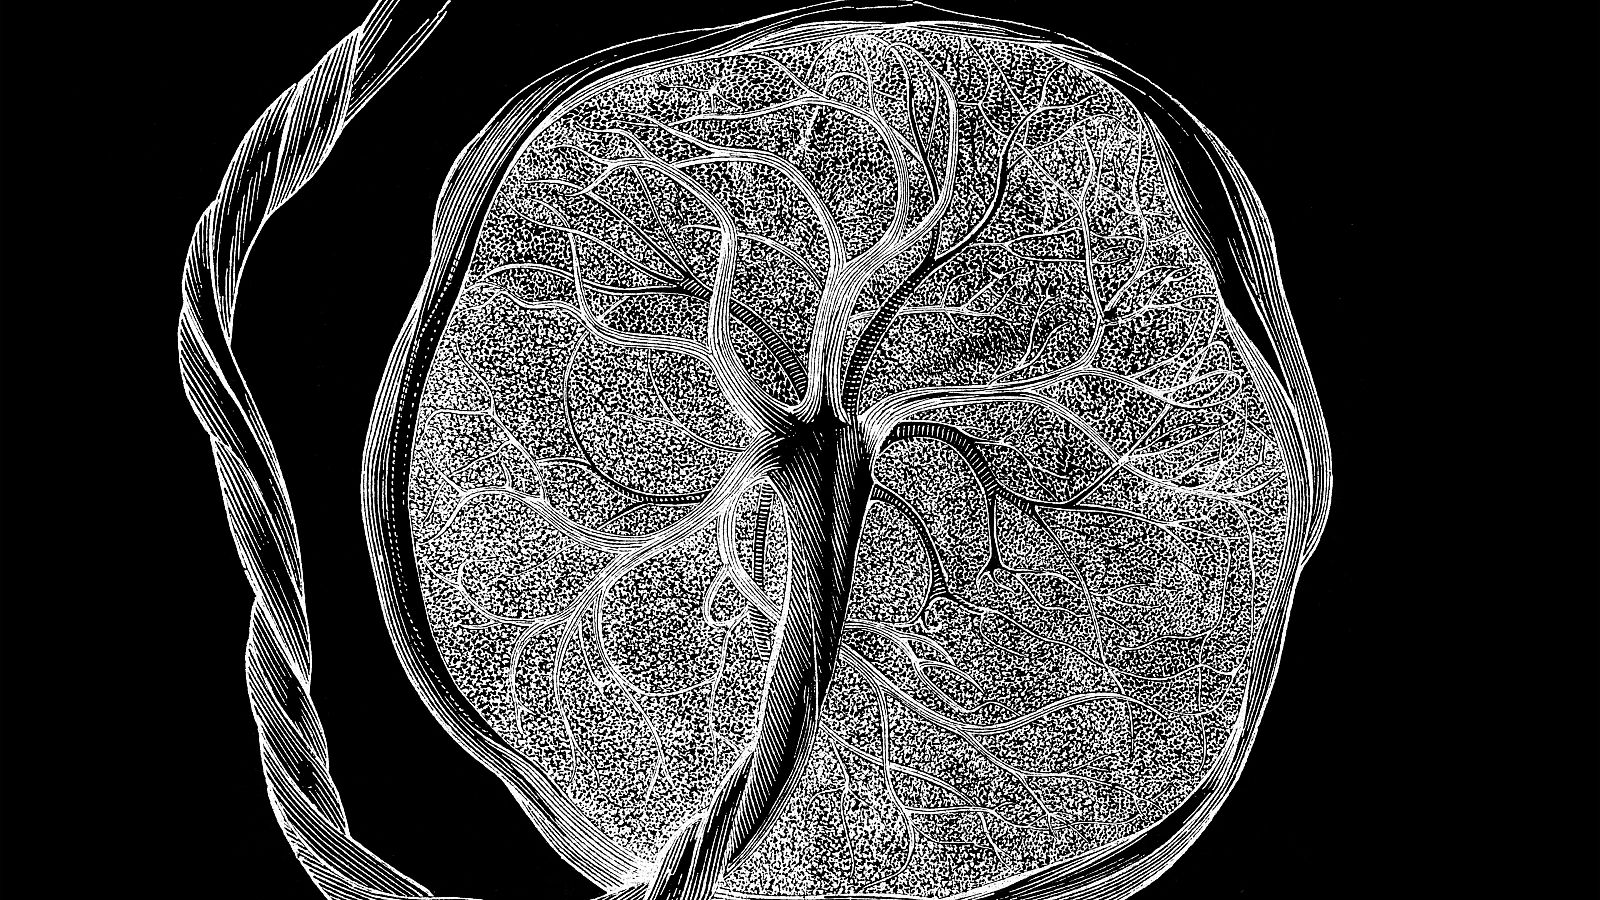

Un equipo científico de los hospitales Clínic y Sant Joan de Déu de Barcelona ha logrado mantener con vida 12 días un feto de oveja en una placenta artificial. El proyecto está pensado para bebés extremadamente prematuros y pretende llegar ahora a las 4 semanas de supervivencia. De los cinco proyectos de placenta artificial que hay en el mundo, éste es el único que se desarrolla en Europa.